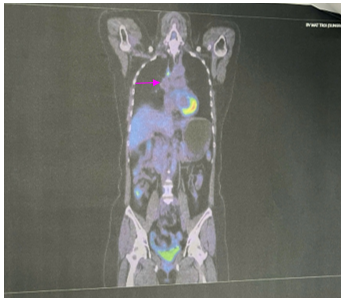

PET CT: Hình ảnh nốt mờ bờ tua gai vùng đỉnh phổi phải kích thước 9x12mm; không tăng chuyển hóa FDG. Hạch cạnh khí quản đoạn thấp kích thước 7x9mm, tăng chuyển hóa FDG (SUV max: 4.83). Chưa phát hiện hình ảnh tăng chuyển hóa FDG khu trú, bất thường tại các vị trí khác trên PET CT toàn thân

Hình 8: Hình ảnh PET CT:  Hạch cạnh khí quản đoạn thấp kích thước 7x9mm, tăng chuyển hóa FDG (SUV max: 4.83). (mũi tên màu hồng)